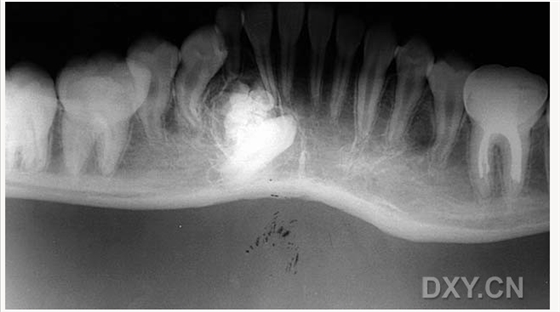

涎石病